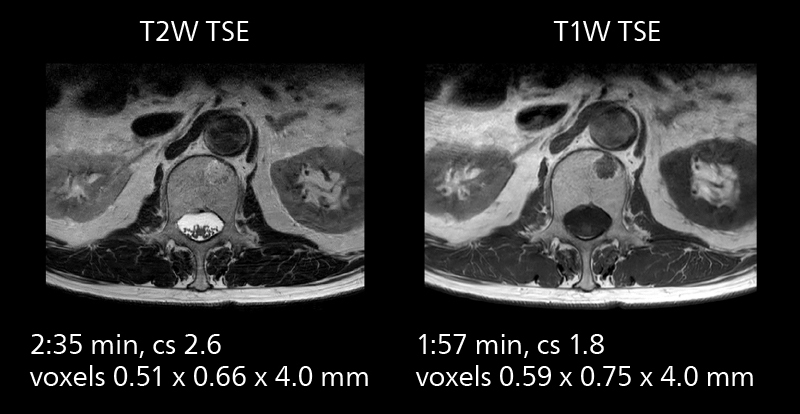

MRI of prostate

Examples of prostate imaging showing faster scan times and improved resolution illustrate the power of SmartPath to Elition X in this case of prostate cancer with PI-RADS score 4.